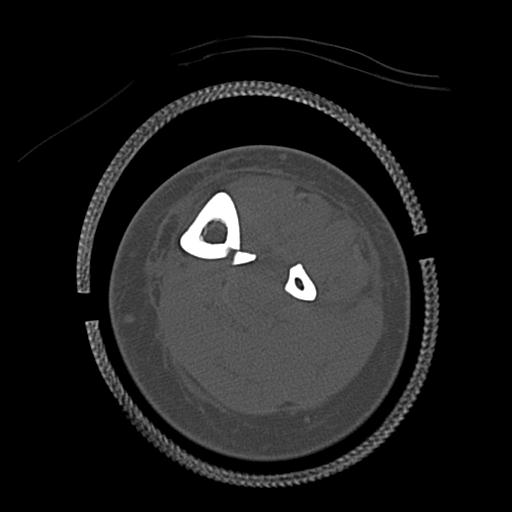

56476 8/28 4R 1/21 2R 左足関節 デジカメ写真 72歳女性 右足関節AS